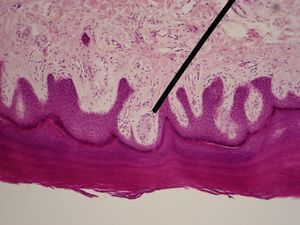

صورة مكبرة مائة مرة